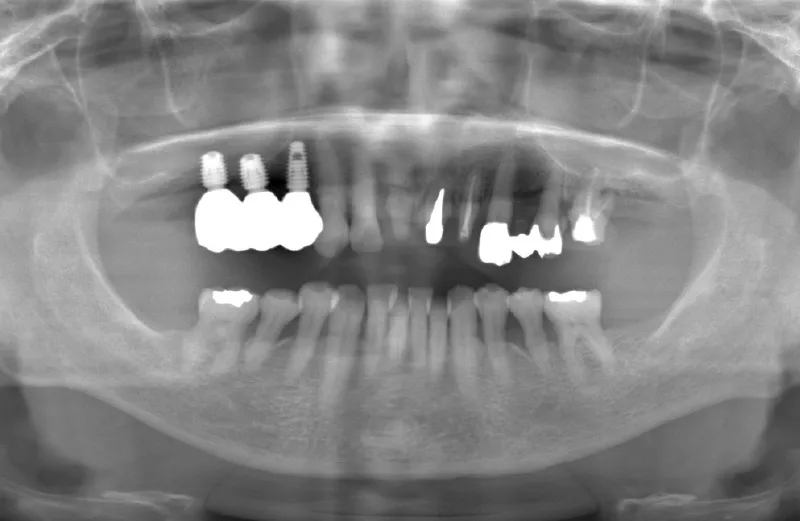

メガジェンオペの症例紹介02

治療前

治療後

| 主訴 | 入れ歯は以前に入れたことがあるが違和感が強く入れられなかった。これ以上歯を失いたくないので右上をインプラントで治療して欲しい。その他の歯もなるべく残して欲しい。 他院では右上は上顎洞までの垂直骨量が2~3mm程度しかないのでサイナスリフトが必須であり、インプラント治療に1年以上かかると言われたのでセカンドオピニオンを希望で来院。 |

| 治療期間 | 2.5ヶ月で仮歯が入り、 4ヶ月で最終補綴物が入って終了。 |

| 治療費 | 約1,500,000円 |

| 治療内容 | エクストラワイドショートインプラントを埋入し、上顎洞を移植材を用いずに挙上しインプラントを埋入した。約2.5ヶ月で仮歯を装着し、様々な機能面に問題がないことを確認し4ヶ月で最終補綴物を装着して終了した。 |

| 治療の リスク |

インプラント埋入オペ時に術者が上顎洞内にインプラントを迷入させる可能性がある。これは術者が技術的に熟練していれば防ぐことが可能。 |